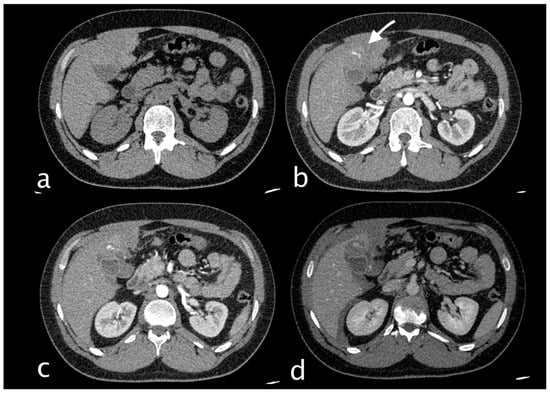

2. Imaging

3.1.3. Imaging and Diagnostic Findings